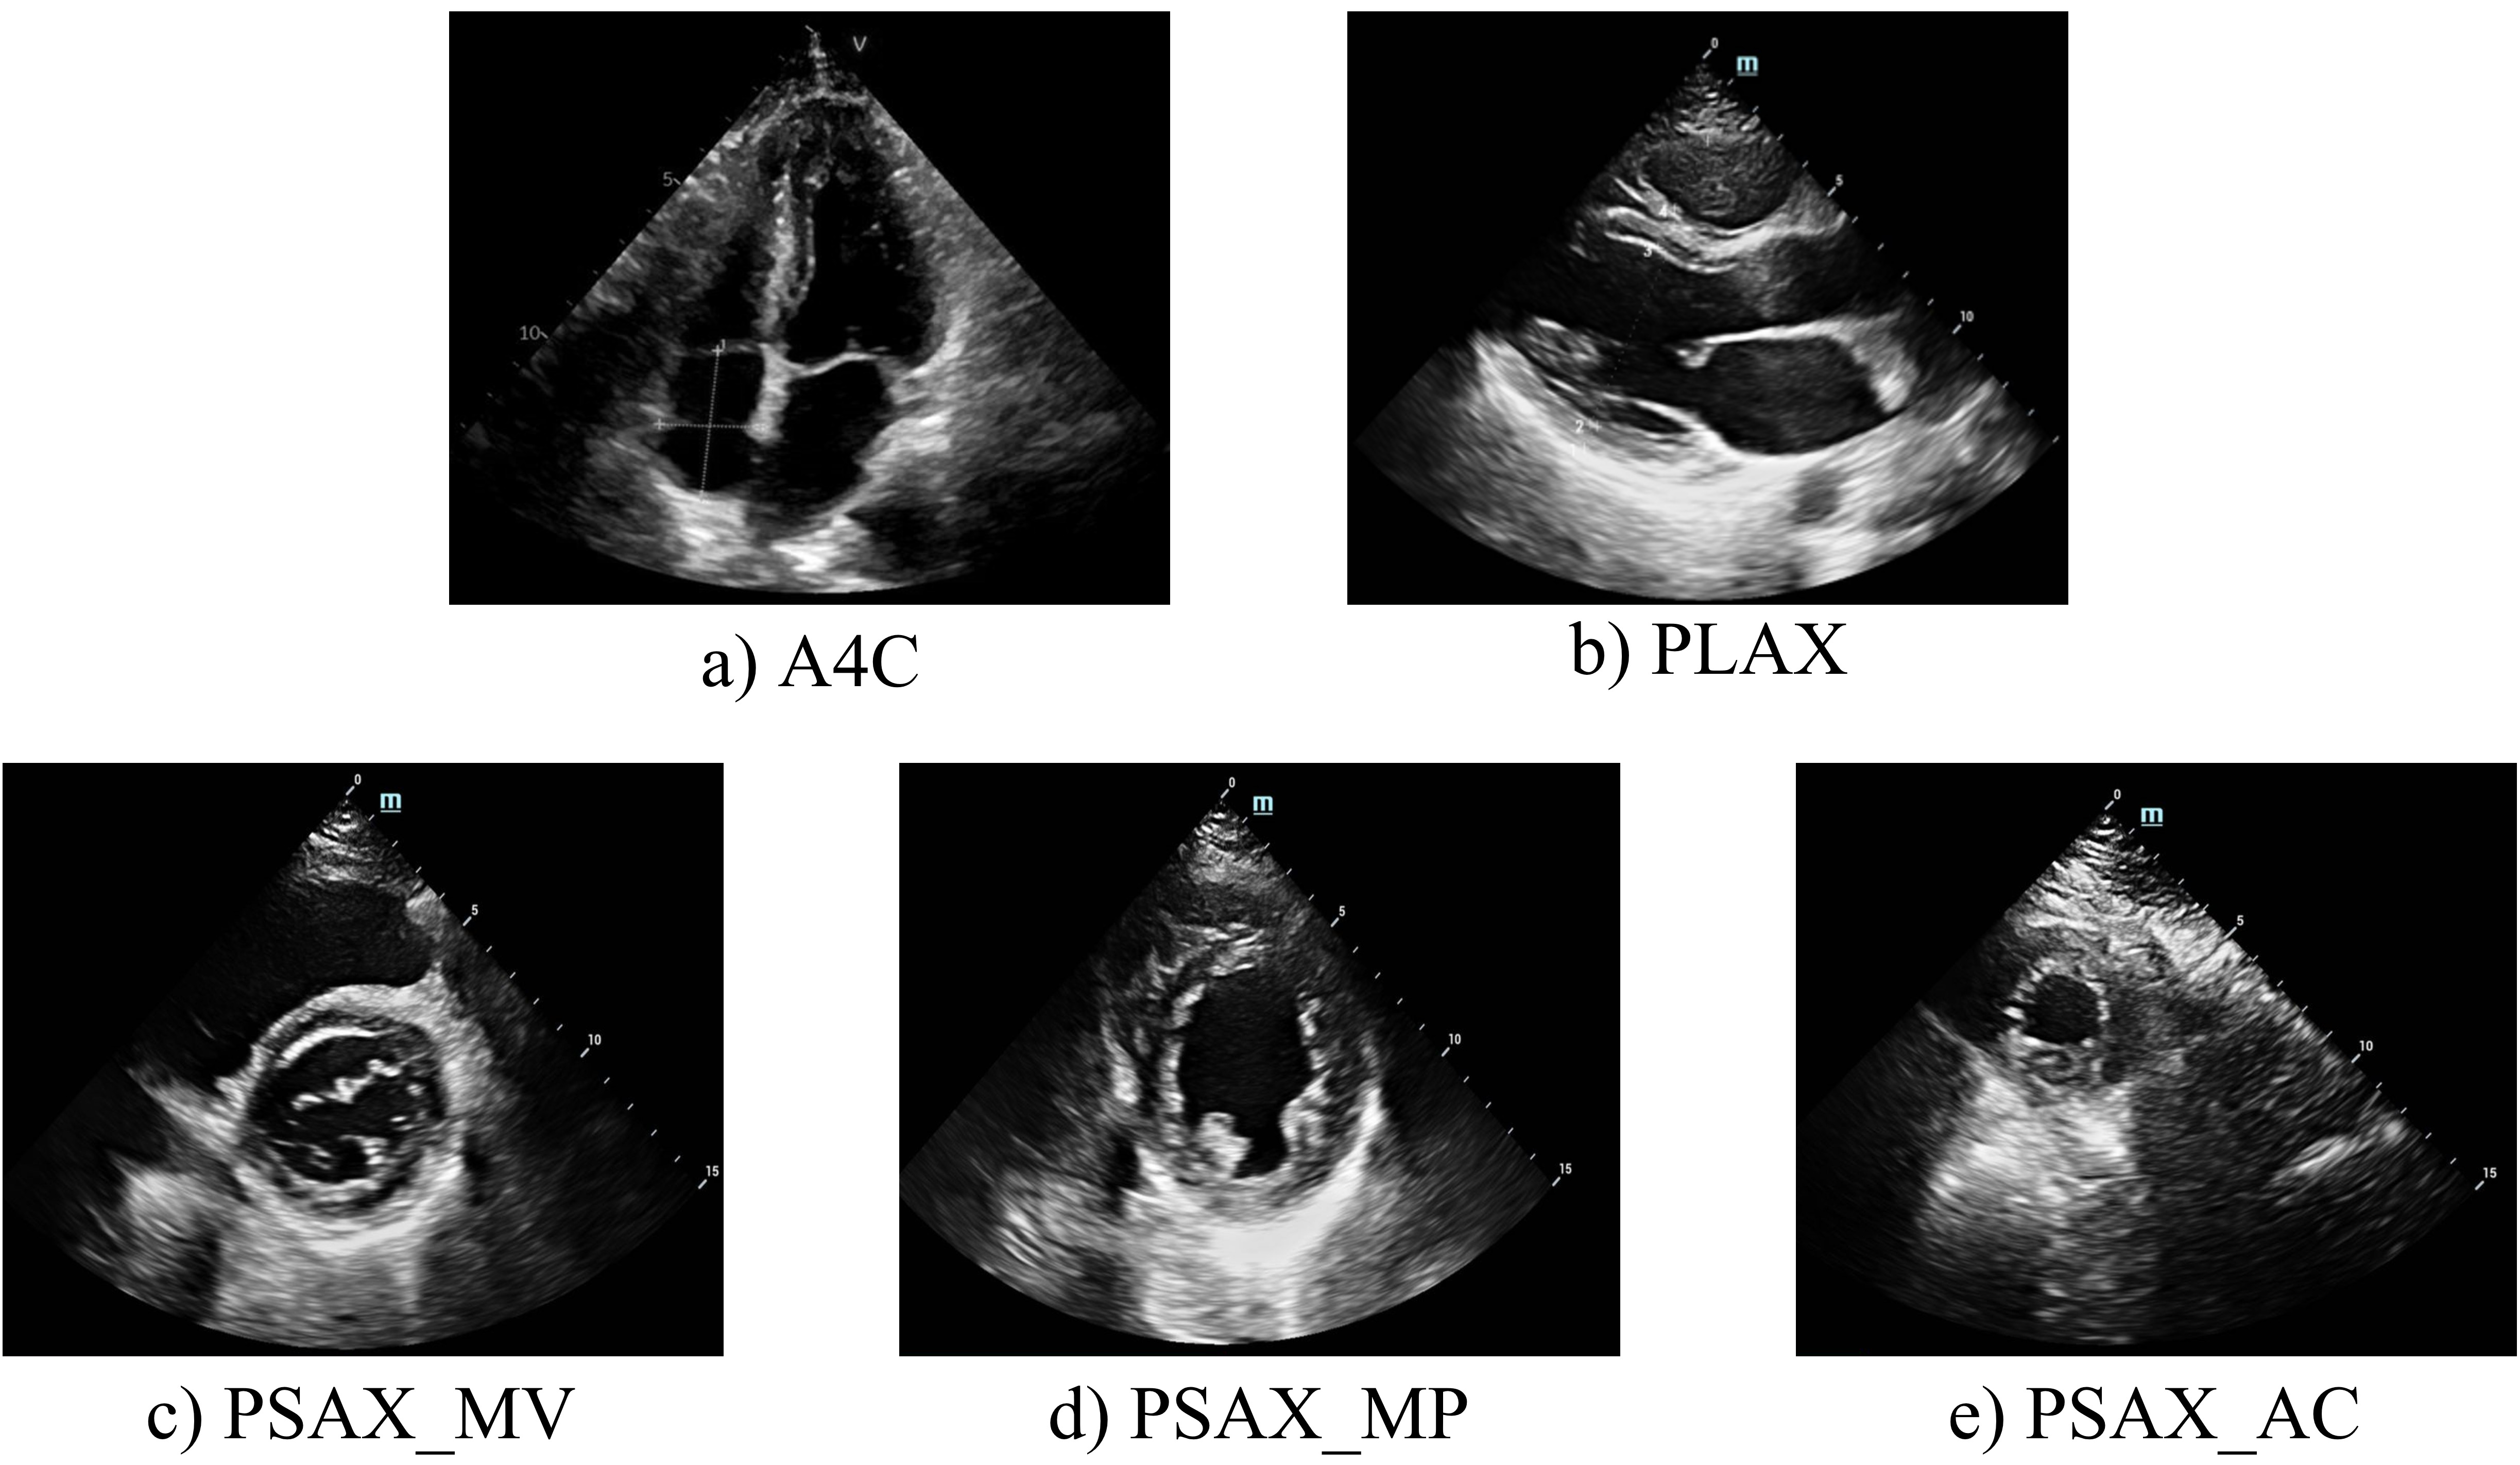

For each patient, five standard echocardiographic views were acquired (Fig. 2), with a set of normal cardiac function(Normal) data serving as the control group. These two-dimensional echocardiograms were captured by skilled echo doctors using various equipment and were stored in JPG format.

Within these five echocardiographic perspectives, the apical 4-chamber (A4C) view (as shown in Fig. 2 a) is particularly effective for evaluating the dimensions of each cardiac chamber and measuring the thickness of the left ventricular wall. The long-axis view of the parasternal left ventricle (PLAX) (Fig. 2 b) is instrumental in examining the left ventricle’s septum and posterior wall, among other structural aspects. This view plays a significant role in detecting various cardiomyopathy forms. The short axis series view of the heart (Fig. 2 c, d, e) provides a detailed perspective on the left ventricle’s wall thickness, echogenicity, motion amplitude, and segmental thickening rate. This comprehensive insight aids in the thorough understanding of the ventricular wall and enhances the identification of specific cardiomyopathy types. By functionally evaluating these views, we aim to distinguish and diagnose HCM and CA by integrating the characteristics observed across the selected five views.